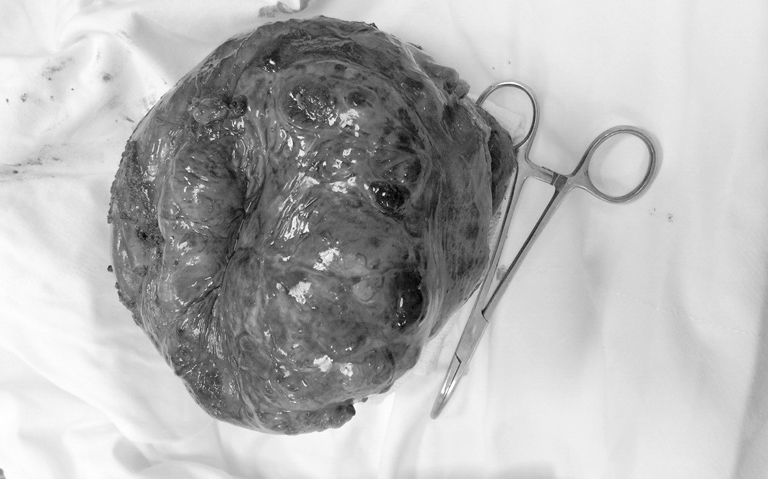

| Khối u dạ dạy 2 kg được bóc tách khỏi cơ thể người bệnh |

Quá trình phẫu thuật, ê-kíp bác sĩ nhận thấy khối u phần đứng bờ cong lớn dạ dày lên đến đáy vị, kích thước u rất to, khoảng 20x12 cm.

U viêm dính vào cơ hoành, dính vào mặt trước tụy, dính chặt vào cuống lách và đuôi tụy nên tiến hành gỡ dính u ra khỏi các cơ quan này.